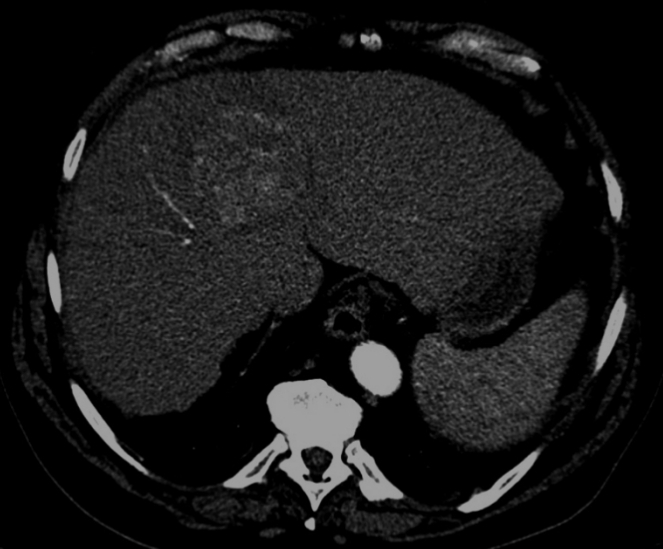

Tdm hépatique C+ temps artériel

Publié par : Kamal nadifi